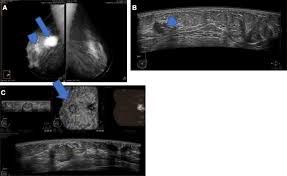

Developing Asymmetry In A Screening Mammogram A Cautionary Tale Of A Missed Cancer Peart 2018 Journal Of Medical Imaging And Radiation Oncology Wiley Online Library

Developing Asymmetry In A Screening Mammogram A Cautionary Tale Of A Missed Cancer Peart 2018 Journal Of Medical Imaging And Radiation Oncology Wiley Online Library from onlinelibrary.wiley.com